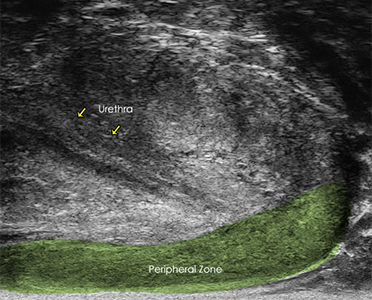

The 29 MHz ExactVuTM system facilities resolution down to 100 microns – and enables

detailed visualization in real-time of the prostate anatomy and characterization of

the prostatic tissue.

The following are select cases that are routinely derived from the ExactVuTM

micro-ultrasound platform and verified with pathological results.